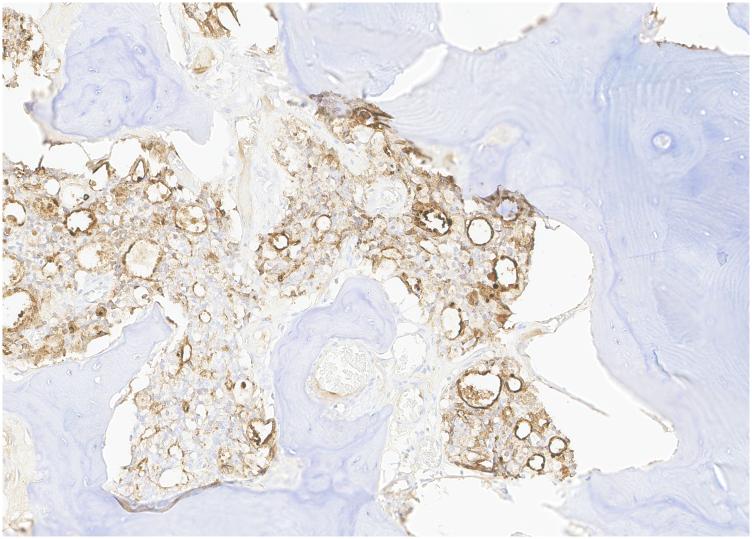

We present a 67-year-old male patient who presented with insidious worsening of right hip pain over a 6-month period with clinical and radiographic evidence of severe osteoarthritis. The patient underwent a primary total hip arthroplasty where the femoral head specimen was sent to pathology as a routine specimen. Pathology results demonstrated metastatic adenocarcinoma of prostate origin. The present case emphasizes the importance of routine pathologic examination of femoral head specimens retrieved during total hip arthroplasty, particularly since this was a clinically unsuspected finding. Although cases like these are rare and the process of routine pathologic examination raises a concern for economic implications, a timely diagnosis of adenocarcinoma provides benefits for the patient, for which cost-benefit ratios are difficult to quantify.

我们报告一名67岁男性患者,其右髋部疼痛在6个月内逐渐加重,临床和影像学检查显示为严重骨关节炎。该患者接受了初次全髋关节置换术,术中取出的股骨头标本作为常规标本送检病理。病理结果显示为前列腺来源的转移性腺癌。本病例强调了在全髋关节置换术中对取出的股骨头标本进行常规病理检查的重要性,尤其是因为这是一个临床未怀疑的发现。尽管此类病例罕见,且常规病理检查过程引发了对经济影响的担忧,但腺癌的及时诊断对患者有益,而成本效益比难以量化。